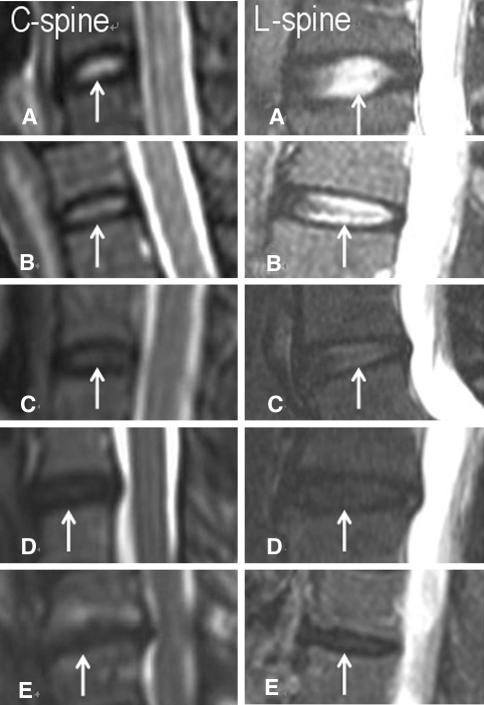

DDD was classified into five grades based on T2-weighted mid-sagittal images depending on the degenerative status of the nucleus. This grading system has been well documented [18, 19] as described below, and each grade is illustrated in Fig. 1.

Homogeneous hyperintense disc; normal disc height

Inhomogeneous hyperintense disc with focal hypointensity (gray); clear distinction between nucleus and annulus.

Inhomogeneous intermediate intensity disc with possible decreased height; unclear distinction between nucleus and annulus.

Inhomogeneous hypointense (dark) disc with decreased height; loss of distinction between nucleus and annulus.

Inhomogeneous hypointense (black) disc with collapsed disc space; loss of distinction between nucleus and annulus.

Fig. 1.

The grading system of cervical and lumbar intervertebral discs based on sagittal T2-weighted images. a Grade I disc (arrow): a homogeneous hyperintense disc with normal height. b Grade II disc (arrow): a hyperintense disc with focal hypointensity. c Grade III disc (arrow): an inhomogeneous disc with unclear distinction between nucleus and annulus. d Grade IV disc (arrow): an inhomogeneous hypointense disc with decreased height. e Grade V disc (arrow): a collapsed hypointense disc